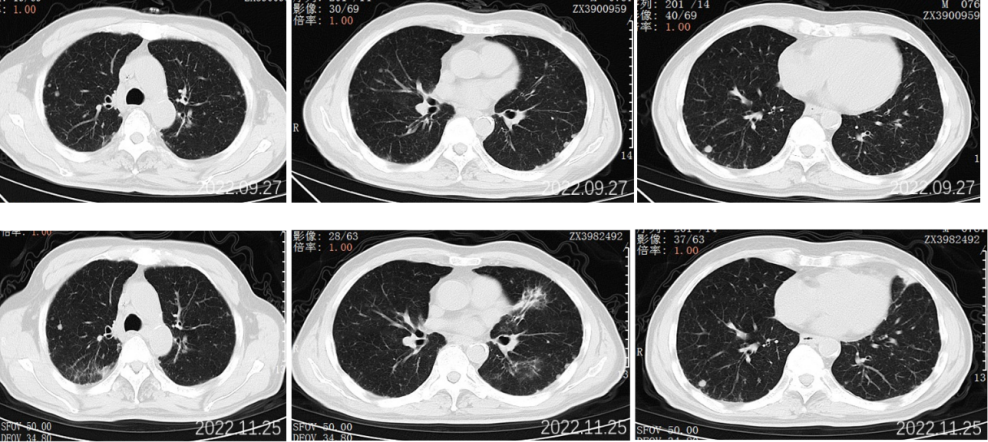

2022.09.27胸部CT平扫:1.两肺多发小结节、类结节影,较前相似,转移性考虑;2.两侧胸腔少量积液较前已吸收。3.左侧第5后肋骨质破坏。

2022.11.25胸部CT平扫:对比2022-09-27影像:1.新见两肺多发间质性肺炎样改变,感染考虑,VP-RADS 2类;2.两肺多发小结节、类结节影,部分较前略缩小,转移性考虑;3.左侧第5后肋骨质破坏,相仿。

2023.5.28胸部CT平扫:对比2022-11-25片:1.两肺散在多发炎症,较前相仿,VP-RADS 2类;2.两肺多发小结节、类结节影,转移瘤考虑,较前相仿;3.左侧第5后肋骨质异常,相仿。男性乳腺发育。

2023.09.29胸部CT平扫:对比2023-05-28片:1.两肺多发小结节、类结节影,较前增多增大,转移瘤考虑。2.两肺散在多发炎症,部分较前吸收;3.左侧第5后肋骨质异常,相仿;4.右侧胸腔少量积液。男性乳腺发育。